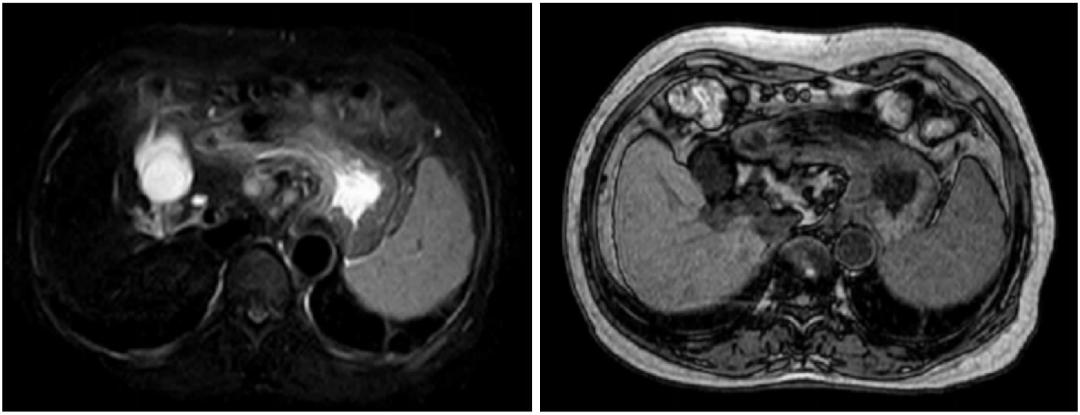

但患者真的是“肝硬化”吗?患者又做了磁共振检查(MRI):

患者做了肝脏病理,肝组织铁染色(++)。

最后真相大白,该患者为继发性含铁血黄素沉着症。过多的含铁血黄色在肝脏沉积,导致肝脏继发的表面不光整,造成“肝硬化”的假象。我们再仔细看肝脏CT图像,肝脏密度升高,明显高于同层面脾脏、腹主动脉管腔密度。

MRI:T1WI、T2WI低信号(“黑肝症”)。